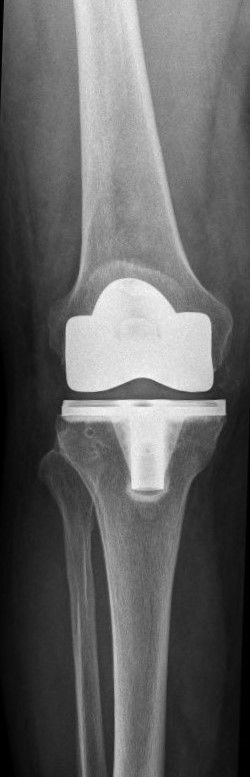

Prothetischer Gelenkersatz (minimalinvasiv) von Hüfte und Knie